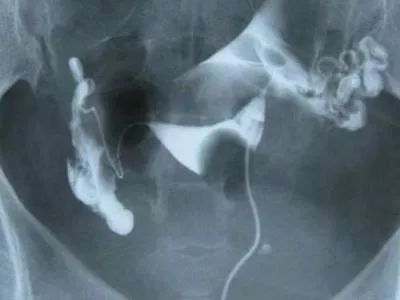

但是如果有过人流或宫腔操作病史,有明显的痛经,或者腹痛不适,甚至*交性**痛,那就要考虑做一下输卵管造影检查,促排卵之前需要先查激素六项,做子宫输卵管造影,输卵管通畅促排卵才有意义。

输卵管完全堵塞、积水等情况是不能促排卵的,促排卵成功排出后发生宫外孕和流产的几率会升高。

如果造影检查提示,输卵管只是轻度的通而不畅,可以试孕4-6个月,因为输卵管造影既有检查作用也有治疗作用,往往轻度粘连引起的通而不畅通过造影剂疏通后变的通畅了。